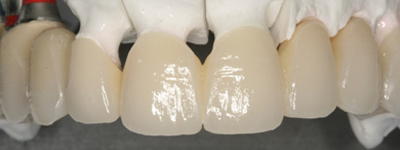

La fresadora dental, en combinación con el escáner más el software de diseño digital de prótesis dentales, son nuestras herramientas más exactas y detalladas para realizar prótesis dentales de máxima precisión y estética.

Utilizamos materiales de alta calidad.